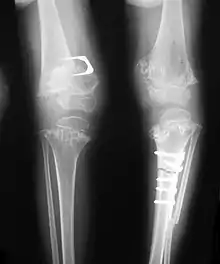

Pseudoachondroplasia. Leg radiographs depicting dysplastic distal femoral and proximal tibial epiphyses, and distal femoral metaphyseal broadening, cupping, irregularities (white arrows) and radiolucent areas especially medially. Note the metaphyseal line of ossification of the proximal tibias (blackarrows) and relative sparing of the tibial shafts. The changes around the knee are known as "rachitic-like changes". Lesions are bilateral and symmetrical.

• Together with rhizomelic limb shortening, the presence of epiphyseal-metaphyseal changes of the long bones is a distinctive radiologic feature of pseudoachondroplasia.

• Dysplastic/hypoplastic epiphyses especially of shoulders and around the knees.

• Metaphyseal broadening, irregularity and metaphyseal line of ossification. These abnormalities that are typically encountered in proximal humerus and around the knees are collectively known as “rachitic-like changes”.

• Radiographic lesions of the appendicular skeleton are typically bilateral and symmetric.